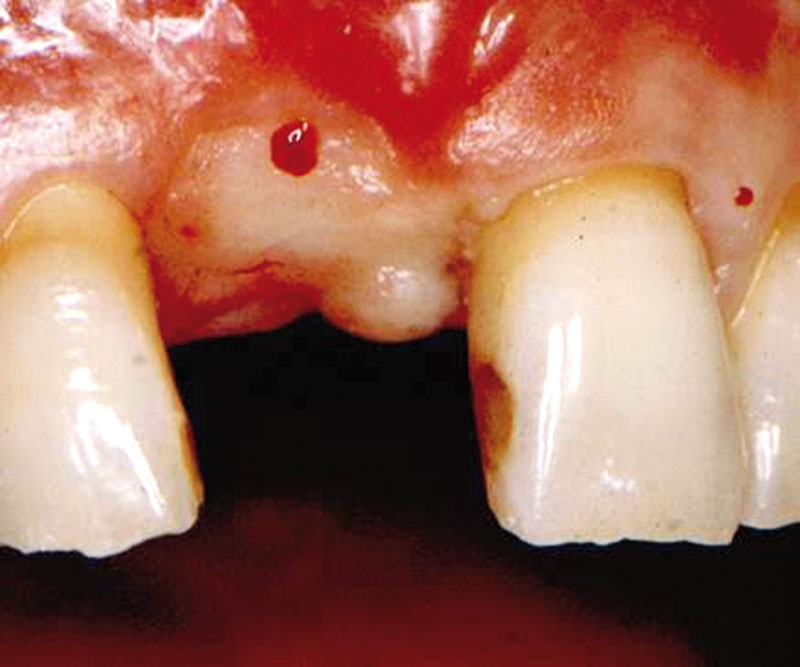

Une fois la vis retirée, un pilier de cicatrisation est mis en place et maintient les deux petites pièces de tissu palatin avant que tout soit suturé par deux points de matelassier avec le lambeau vestibulaire…